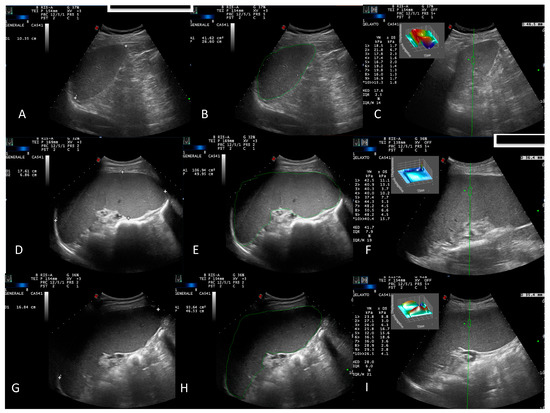

- B-mode US evaluation of the liver, spleen, kidneys, gallbladder, pancreas, bladder, and retroperitoneal and splanchnic abdominal vessels (splenic and portal veins) [15]. US measurements of the liver and spleen were performed and expressed in cm, as previously described [16]. A patient’s spleen was evaluated in supine decubitus through the intercostal window. The US window, which included the splenic hilum, was considered optimal for biometric measurement of the organ. Measurements of the splenic longitudinal diameter (SLD) and cross-sectional area (CSA) were expressed in cm and cm2, respectively (Figure 1A,B,D,E,G,H). An SLD up to 11–12 cm in the cranio-caudal length and a CSA < 45 cm2 were considered normal [17], while moderate and marked splenomegaly were defined as a CSA in the range of 45–65 cm2 and >65 cm2, respectively [18];